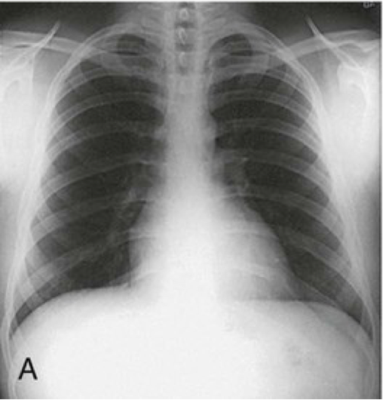

Question 11

Question

Identify the body habitus.

Answer

• Hypersthenic

• Sthenic

• Hyposthenic

• Asthenic